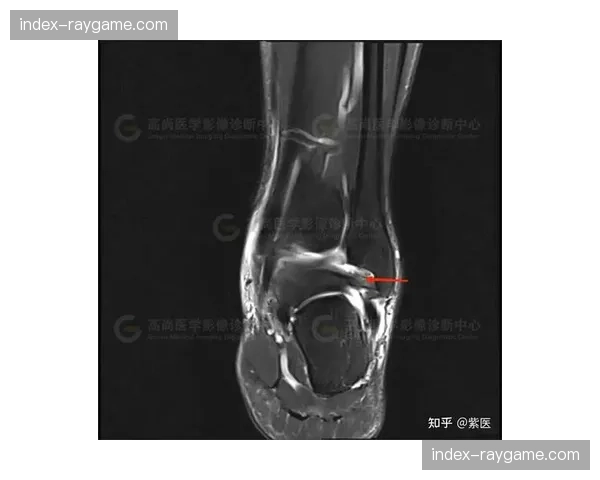

里昂中场球员马克西姆·卡克雷因脚踝韧带损伤将缺席六周,这一消息在本轮法甲联赛中引起广泛关注。卡克雷在比赛中受伤后立即接受了详细的医疗检查,结果显示他的脚踝韧带受到了严重损伤。里昂俱乐部官方宣布,卡克雷将进行为期六周的康复治疗,这意味着他将错过接下来的几场关键比赛。作为球队中场的重要组成部分,卡克雷的缺席对里昂的战术安排和比赛节奏可能会产生显著影响。球迷们对此感到遗憾,同时也希望他能够尽快恢复健康,重返赛场。